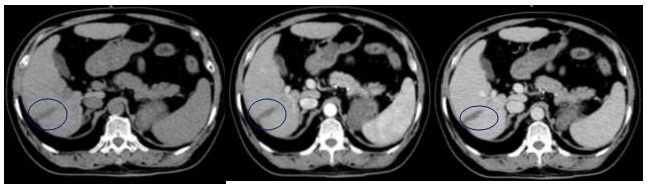

Hình 8: Hình ảnh CT ổ bụng sau 24 tháng: Vùng giảm tỷ trọng hạ phân thùy VI, KT 3,0×1,0cm, không ngấm thuốc, gây co kéo bờ gan (vòng tròn tím)

Hình 9: Hình ảnh CT ổ bụng sau 36 tháng: Vùng giảm tỷ trọng hạ phân thùy VI, KT 2,9×1,0cm, sau tiêm không ngấm thuốc, co kéo bờ gan (vòng tròn xanh đậm)

Nhận xét: Trước điều trị khối u ngấm thuốc điển hình của HCC (hình 5), tuy nhiên sau điều trị ở thời điểm 9 tháng trở đi khối u giảm về kích thước, không ngấm thuốc sau tiêm nên đạt được bệnh đáp ứng hoàn toàn theo tiêu chuẩn mRECIST (hình 6,7,8,9).